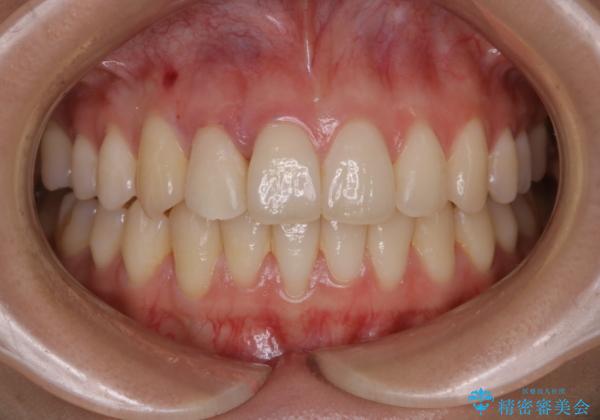

非抜歯でも劇的変化 インビザライン矯正治療

歯のガタつきを治すため矯正治療を希望。審査の結果、非抜歯での矯正が可能であるという見通しが立ったためインビザラインによる非抜歯矯正治療を行った。

歯を並べるスペースを作るために、歯の遠心移動と歯列の拡大、歯自体を少しだけ小さく削る(IPR)という方法を複合的に組み合わせて配列を行いました。遠心移動用のゴムかけにはマイクロインプラントという小さいネジを用いて骨に直接固定源を求めました。